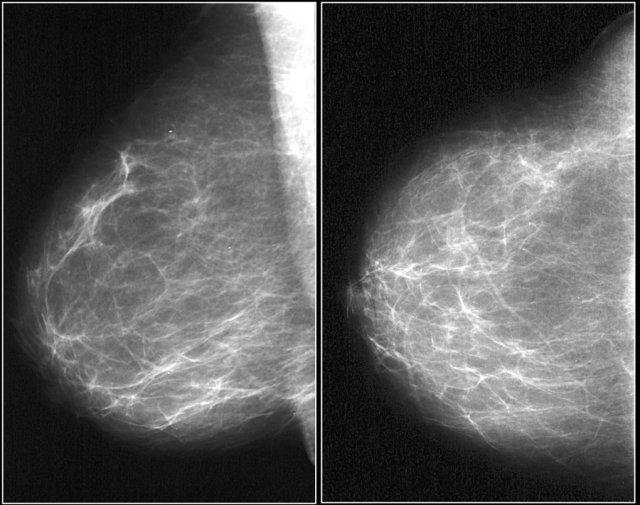

Đây là hình ảnh một khối tăng tỷ trọng với hình dạng không đều và bờ tua gai.

Lưu ý hiện tượng co rút da khu trú.

Trường hợp này được phân loại BI-RADS 5 và được xác nhận là ung thư biểu mô tuyến vú xâm lấn.